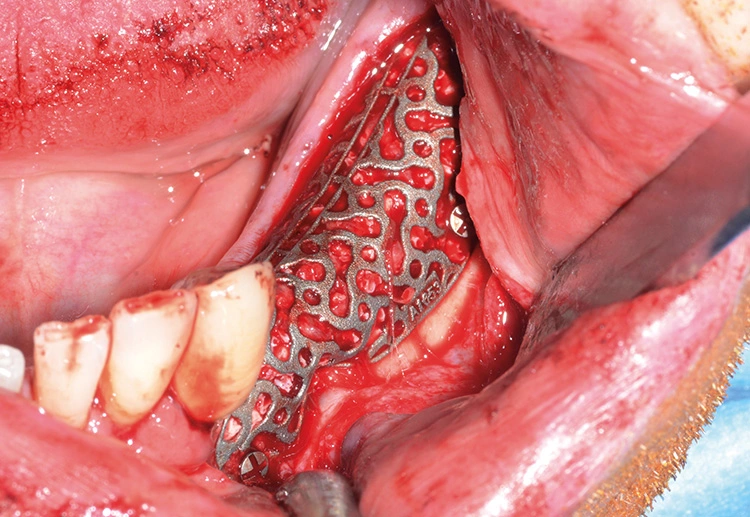

Präoperativ wurde im Sinne eines Backward Planning erst die spätere Implantatposition und in Kenntnis dieser, die Ausdehnung des Titangitters festgelegt. Hierbei wurde festgestellt, dass sich zum einen das Foramen mentale direkt im Augmentations- und Implantationsbereich befindet und zum anderen der Verlauf des Nervus alveolaris inferior, trotz Augmentation, nur relativ kurze Implantate zulassen wird.

Bei der digitalen Planung des Gitters wurde dieser Aspekt besonders berücksichtigt und zudem auf die Lage des Foramen mentale speziell geachtet. Das Gitter wurde im Austrittsbereich ausgespart, um eine Traumatisierung zu vermeiden (Abb. 4-19).

Trotz der schlechten, hart- und weichgewebigen Grundvoraussetzungen konnte der Kieferkamm zufriedenstellend rekonstruiert werden. Die Augmentation des kombinierten, horizontalen und vertikalen Defekts mit Yxoss CBR®, Geistlich Bio-Oss®, Geistlich Bio-Gide®, autologem Knochen und PRF ermöglichte die Implantation mit hoher Primärstabilität in den rekonstruierten Bereich.